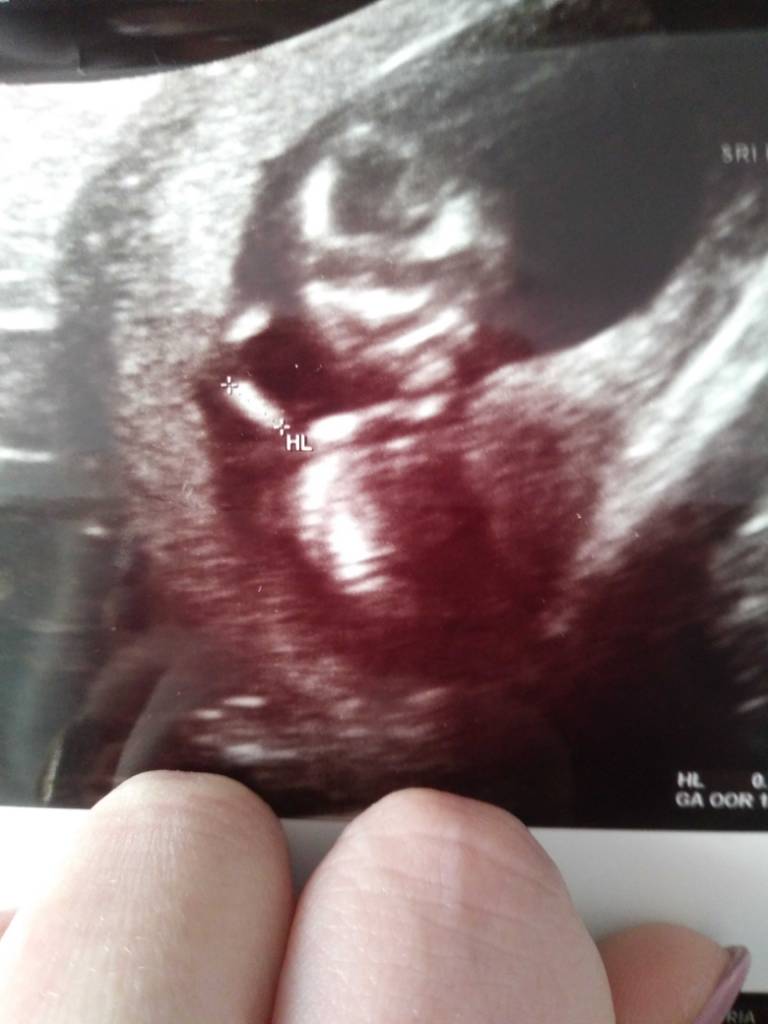

Płeć nieznana, crl 6.77 więc jakby 13+1 a nie 12+4, obwody brzuszka i glowki w normie, długości kosci nozek i rąk też, przeziernosc 1.4 [emoji4]nosek w porządku, serducho, żołądek, nerki i pęcherz też, waga chyba 61g. Spr jeszcze ilość wód i to by było na tyle. W środę wyniki papa i wizyta u genetyka.Zobacz załącznik 920272

No ja już po :) wszystko jest ok, maleństwo ma 6,5 cm. Przezierność karczku to 1,5. Wychodzi że to 12t6d :) płeć niestety nie znana, bo się maleństwo bokiem odwróciło :p Zobacz załącznik 920356